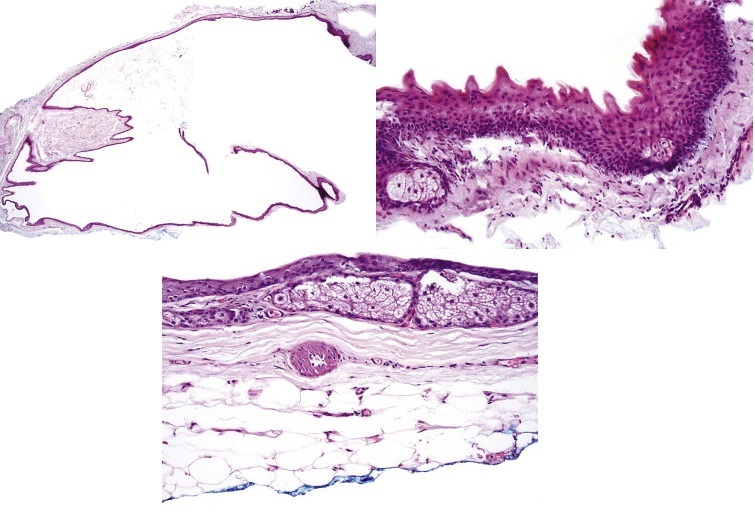

Syringocystadenoma Papilliferum: 33% arise in association with a nevus sebaceous, 10% may coexist with a BCC or trichoblastoma. A subset of cases has a deletion of 9q22 PTCH gene and 9q21 (p16). Histologically they present as surface invagination of glandular cords composed of one to two layers of cuboidal cells associated with a fibrovascular stroma with numerous plasma cells. Cystic spaces may form within which are free floating islands which are peripherally lined by cuboidal cells with an inner core composed of loose connective tissue, blood vessels and numerous plasma cells.

Fig 1 Syringocystadenoma papilliferum. Characteristic low-power morphology of a squamous epithelial border enclosing tall papillary projections with a dense infiltrate within their cores.

Fig 2 Syringocystadenoma papilliferum. The epithelium is double layered and the underlying stroma is rich in plasma cells.

Fig 3 Syringocystadenoma papilliferum. Superficially, the double-layered apocrine epithelium is replaced by squamous epithelium